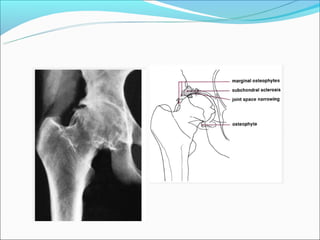

Osteofitóse

Esclerose

Redução do espaço

articular